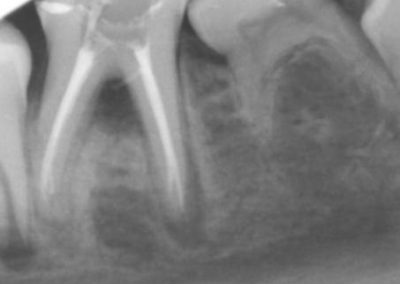

Pathological changes occur in the tooth due to trauma or caries progression which can, in turn, cause bacteria to invade the root canal system.

During the consultation, the dentist will first listen to your concerns and carry out appropriate tests to identify the right tooth that is causing pain. As a part of the diagnosis, your dentist will carry out various clinical tests to identify the right tooth and will take some radiographs which can aid in the diagnosis.

An access cavity is placed on the surface where the patient bites, to reach the root canals of the tooth. Once all the canals are identified, small files are used to remove the infected pulp.

Files of different sizes are used to eliminate bacteria and infection and to shape the canals. The canals are disinfected thoroughly with irrigants and later the canals will be sealed in 3 dimensions with a special medicament called gutta-percha to prevent reinfection of the tooth and the access cavity will be sealed with a temporary filling.